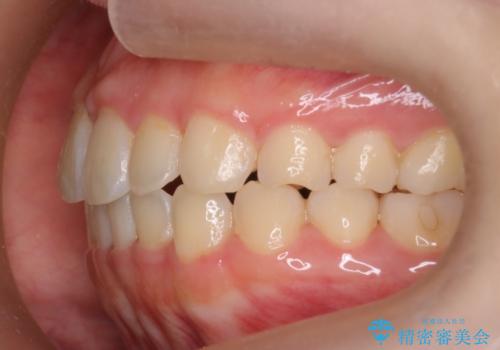

【インビザライン】前歯の凸凹をなおしたい

- 前歯のガタガタを主訴に来院されました。

インビザラインで綺麗な歯並びになり、患者さんには大変満足していただきました。

インビザラインは軽度叢生治療において優れた選択肢となります。